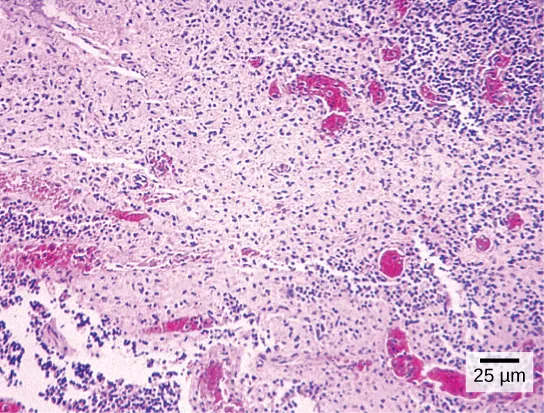

Have you ever heard of a medical test called a Pap smear (Figure 3.4)? In this test, a doctor takes a small sample of cells from the uterine cervix of a patient and sends it to a medical lab where a cytotechnologist stains the cells and examines them for any changes that could indicate cervical cancer or a microbial infection.

Cytotechnologists (cyto- = cell) are professionals who study cells through microscopic examinations and other laboratory tests. They are trained to determine which cellular changes are within normal limits or are abnormal. Their focus is not limited to cervical cells; they study cellular specimens that come from all organs. When they notice abnormalities, they consult a pathologist, who is a medical doctor who can make a clinical diagnosis.

Cytotechnologists play vital roles in saving people’s lives. When abnormalities are discovered early, a patient’s treatment can begin sooner, which usually increases the chances of successful treatment.

Both normal cells and cells infected with HPV have an irregular, round shape and a well-defined nucleus. The infected cells, however, are two to three times as large as uninfected cells, and some have two nuclei.

Figure 3.4 These uterine cervix cells, viewed through a light microscope, were obtained from a Pap smear. Normal cells are on the left. The cells on the right are infected with human papillomavirus. (credit: modification of work by Ed Uthman; scale-bar data from Matt Russell)